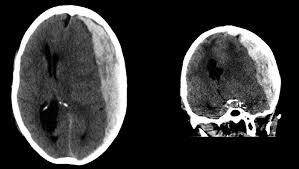

How Is It Diagnosed?

Symptoms can vary: some people may feel well, while others may become confused, agitated, or lose consciousness.

If a subdural haematoma is suspected, doctors at NNRC will perform a CT scan of the head to look for blood and determine the severity of the bleed.